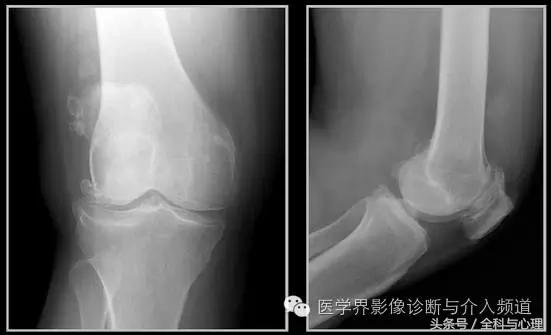

五、滑膜软骨瘤病

1°少见,病灶数量多,大小均匀,相邻关节正常。

2°多见,病灶数量少,大小不一,多伴有退行性骨关节病。

软组织钙化与骨化,软组织钙化和骨质增生 滑膜骨软骨瘤病 1°

软组织钙化与骨化,软组织钙化和骨质增生 滑膜骨软骨瘤病 2°

软组织钙化与骨化,软组织钙化和骨质增生 滑膜骨软骨瘤病